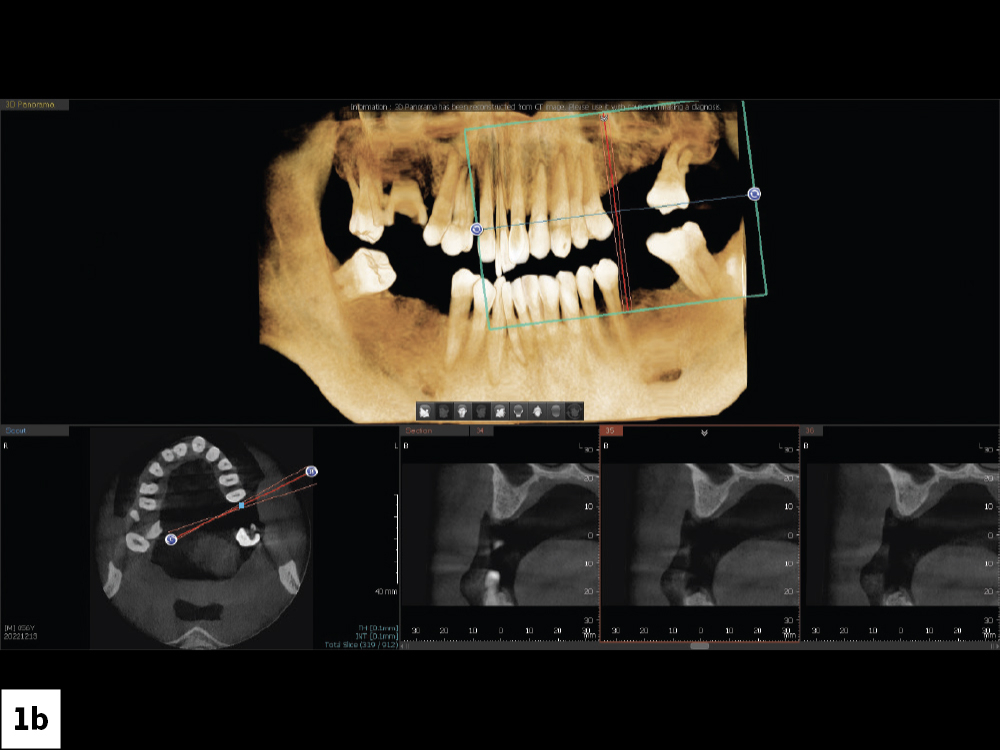

Figures 1a, 1b: The desire for improved esthetics motivated the patient to seek consultation. A retracted view shows the patient’s anterior misalignment and malocclusion in the maxillary arch. CBCT analysis showed extensive periodontal bone loss that warranted extraction and implant reconstruction in the maxilla and posterior mandible.